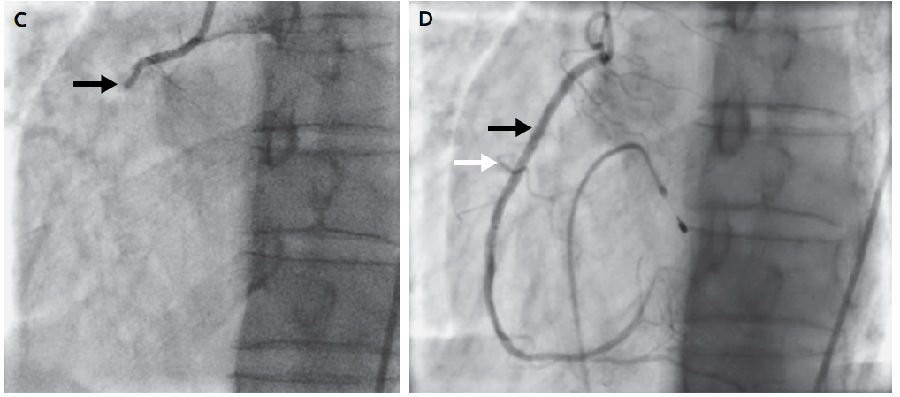

给予静脉输液,经静脉植入临时起搏导线。冠脉造影显示右冠状动脉靠近右心室分支处闭塞100%(图C,箭头)。经PCI治疗后,右冠状动脉(图D,黑色箭头)和右心室分支(图D,白色箭头)血流恢复。